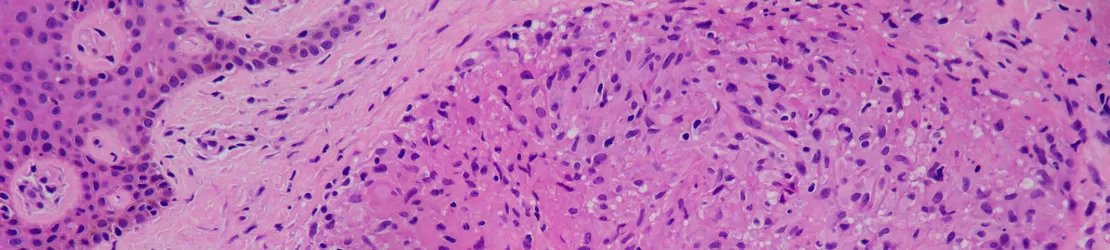

imagine a sarcoidozei pielii la microscop

Sarcoidoza este, de obicei, diagnosticată printr-o combinație de examen fizic, imagistică (radiografie toracică) și biopsie a granuloamelor suspectate. Deoarece sarcoidoza poate arăta ca alte afecțiuni, medicul specialist poate efectua teste suplimentare pentru a exclude alte boli.

• biopsii: pot fi efectuate în multe moduri diferite, în funcție de locul în care apar granuloamele. Biopsiile de piele, conjunctive (ochi) și cele din ganglionii limfatici pot fi neinvazive sau minim invazive.